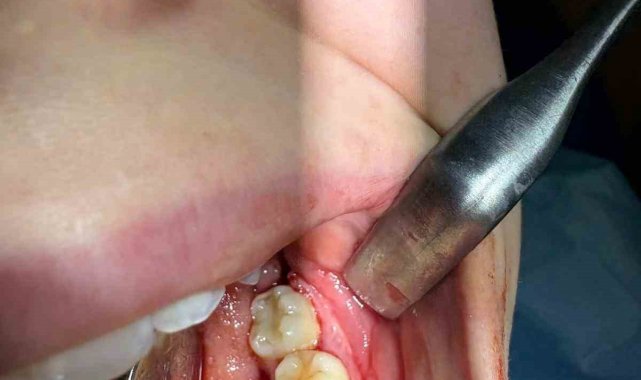

İleri düzey çürük nedeniyle daimi azı dişi çekilen hastaya, yaşı gereği çene gelişimi devam ettiği için klasik implant tedavisi uygun görülmedi. Bunun yerine, hastanın ağzında gömülü halde bulunan yirmi yaş dişi, uzman ekip tarafından cerrahi operasyonla çıkarılarak çekilen dişin yerine nakledildi.

Operasyon sırasında, dişin sağlıklı bir şekilde tutunmasını sağlamak için hastanın kendi kanından elde edilen PRF (Platelet Rich Fibrin) materyali, nakil öncesi hazırlanan diş yuvasına yerleştirildi. Bu uygulama, doku iyileşmesini hızlandıran ve hücre yenilenmesini destekleyen doğal bir yöntem olarak öne çıkıyor. Bu tedavi yöntemi, hastanın kendi dişi kullanıldığı için doğal görünüm, uyum ve fonksiyon açısından büyük avantaj sağlıyor. Aynı zamanda, vücut tarafından kabul edilme oranı yüksek olduğundan, uzun vadeli başarı şansı da oldukça yüksek.

Operasyon, Karabük Üniversitesi Diş Hekimliği Fakültesi Endodonti Anabilim Dalı Öğretim Üyesi Doç. Dr. Olcay Özdemir ve Ağız, Diş ve Çene Cerrahisi Anabilim Dalı Öğretim Üyesi Dr. Öğr. Üyesi Muhammed Abdullah Çege tarafından başarıyla gerçekleştirildi.